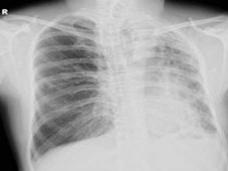

肺先天性发育不全可根据其发生程度分为3 类:肺未发生(agenesis):一侧或双侧肺缺如;肺未发育(aplasia):支气管原基呈一终端盲囊,未见肺血管及肺实质;肺发育不全(hypoplasia):可见支气管、血管和肺泡组织,但数量和(或)容积减少。严重病例出生后即死亡。主要表现为呼吸困难,甚至呼吸窘迫,以及长期反复呼吸道感染,体检可见患侧胸廓塌陷,活动度减弱,叩诊呈浊音,听诊呼吸音减低或消失。